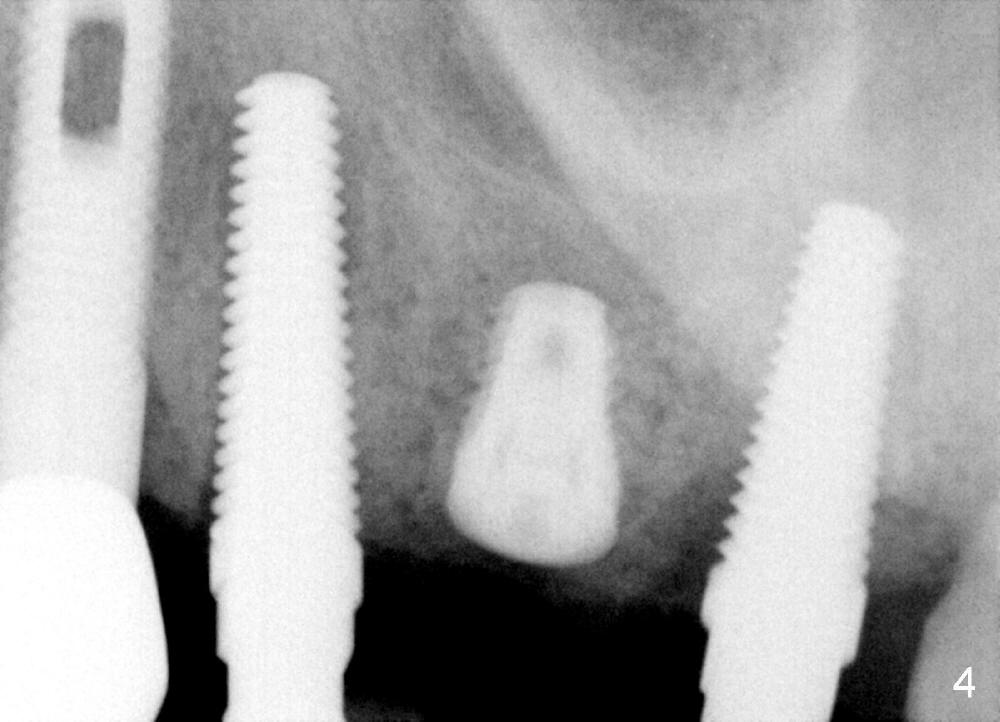

A 84-year-old man has a failing bridge.  A short implant was placed at the pontic site 5 months ago (Fig.1, taken 2 months postop).  The bridge was temporarily recemented.  It is planned at next appointment to extract #13, uncover the implant at pontic and save #15 if possible.  When the bridge is removed, the tooth #15 is also found non salvageable (Fig.2). The root stump of #15 is oval, 5x10 mm.  Preop PA shows that the 2nd molar has two roots (Fig.1: *).  When the tooth is extracted, the septum is found wide buccolingually (Fig.3: S, between the buccal (B) and palatal (P) sockets).  Osteotomy is formed in the septum with combination of drills and osteotomes, followed by insertion of taps (Fig.4).  Finally the osteotomy (Fig.5 O) in the septum (S) of #15 deviates into the buccal (B) socket.  When the implant is placed (Fig.6), it deviates buccally slightly (Fig.7).  The remaining sockets are filled by bone graft (Fig.7 G).  Immediate provisional bridge is fabricated after placement of abutments (A).  The main purpose of the provisional at early stage is to hold bone graft in place.  There is no occlusal contact with the opposing dentition,  Due to time constraint, the uncovering of #14 is postponed.  The provisional dislodges 2-3 days postop.  The patient returns for recementation 5 days postop; the sockets have initially healed (Fig.8,9, as compared to Fig.7).